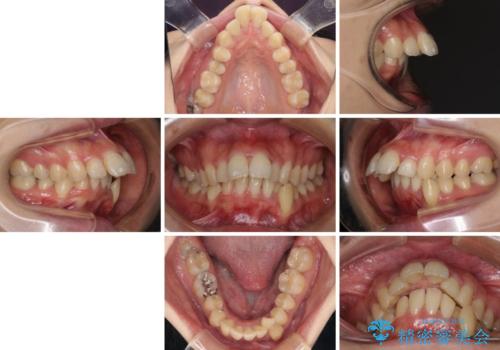

- 口元がひどく突出するくらいの上顎前突を気にして来院された患者様です。

舌の突出癖が顕著で、上顎歯列は完全なV字型となっている状態でした。

下顎歯列にも八重歯があり、上下左右の第一小臼歯4本を抜歯して、ワイヤー装置にて矯正治療を行うこととしました。

どこまで口元の突出感を改善できるのか不安でしたが、舌のトレーニングをしっかりと行ってくださり、我々も驚くほど劇的に改善することができました。